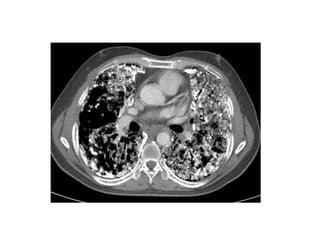

-(A) Markedly enlarged

pulmonary arteries with

tiny branching smaller

vessels

-(B) Enlarged right ventricle

and the smaller left

ventricle , the septum is

pushed towards the left

ventricle due to very high

pressure inside the right

ventricle